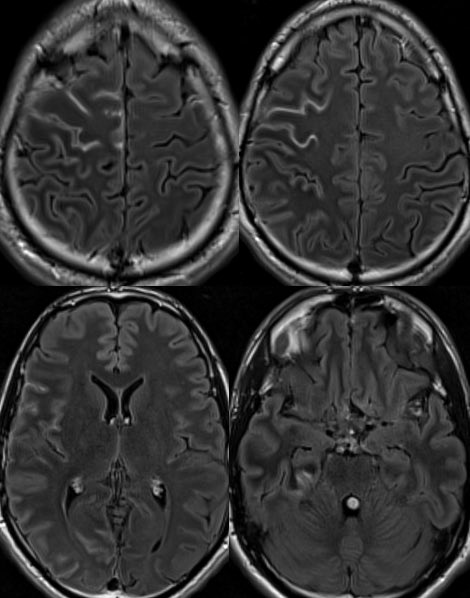

🔷Typical Imaging of MOG-AAD:

▶️BRAIN findings: Occur in <50% of patients though tend to involve the deep gray matter and infratentorium (particularly in children)

▶️Patterns include ADEM-like or CLIPPERS-like imaging features

▶️Leptomeningeal enhancement can also be seen in association with FUEL & FLAMES x.com

🔷A distinct subtype/clinicoradiographic syndrome of MOGAD is a cortical encephalitis presenting with headache, fever and seizures known as FLAMES of MOGAD🔥

🔷When the predominant imaging features are leptomeningeal enhancement with little to no cortical involvement, this is considered FUEL of MOGAD ⛽️ x.com

🔷FUEL ⛽️& FLAMES 🔥

▶️Imaging: Unilateral (more common) or b/l cortical swelling (🔥) or isolated leptomeningeal enhancement (⛽️) +/- other features of MOGAD